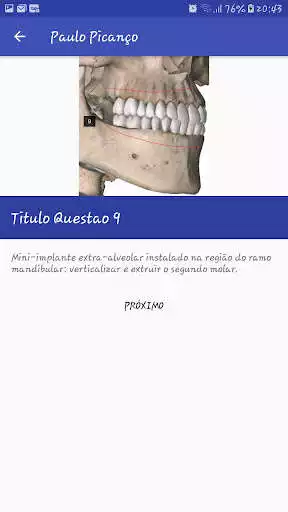

Com este aplicativo o ortodontista poderá optar por uma das localizações ou a combinação de mini implantes visando otimizar o tempo e os resultados do tratamento ortodonticoUpdates: